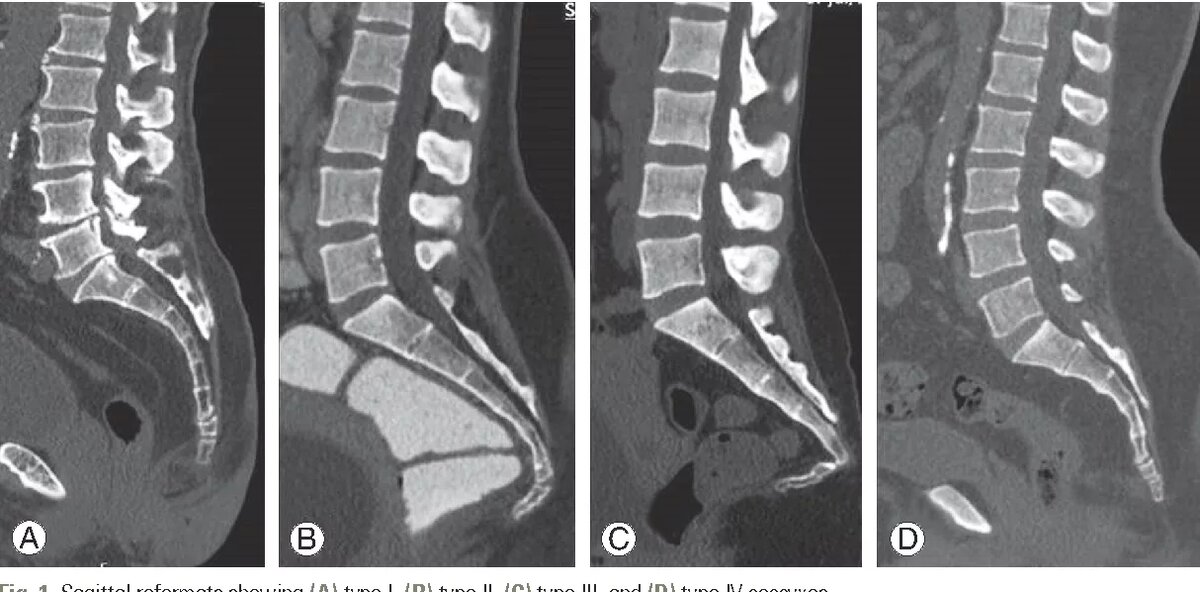

На МРТ, КТ или рентгеновском исследовании находят отклонение копчика вперед.

-2

Раньше предполагали, что копчик смещался в результате травмы, в настоящее время преобладает мнение о напряжении мышц тазового дна, являющихся причиной сгибания копчика вперед.